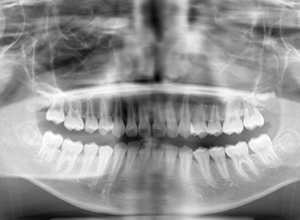

X-Ray

X-Ray所見

セファロ所見 下顎骨はしっかりとしているが顎顔面の奥行きに比べて下顔面高さが低い。頭蓋に対して上顎骨は前方位にあり、上下顎骨の前後的位置関係のズレは大きかった。